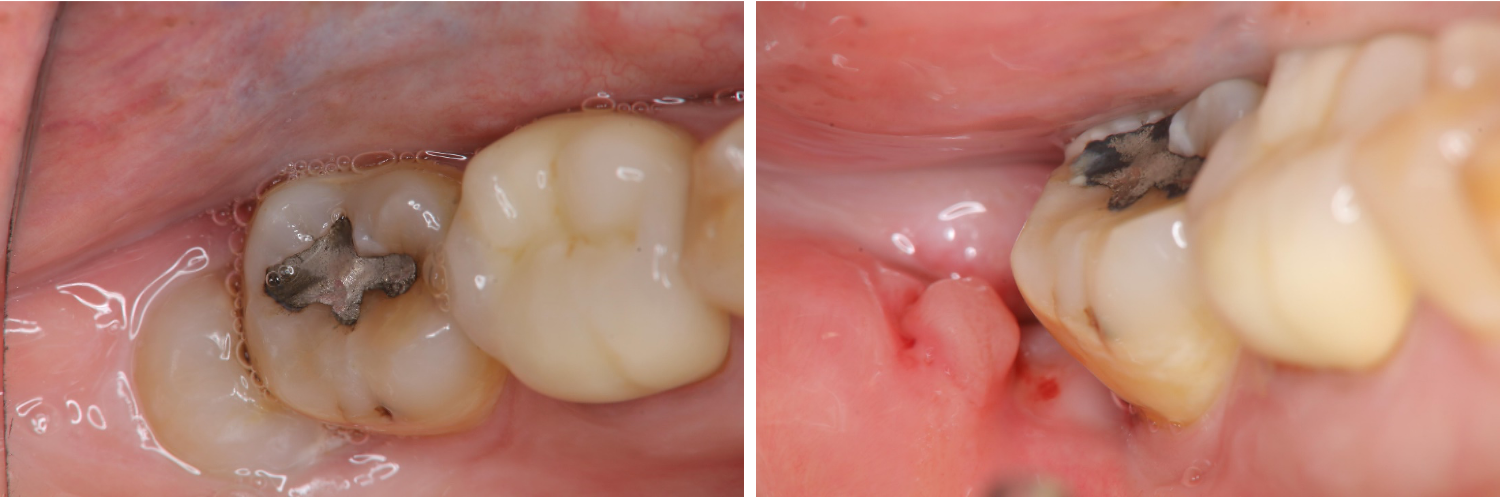

術前、術後比較